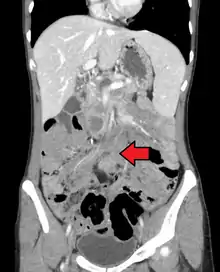

![]() | |

Desmoid tumor as seen on CT scan | |